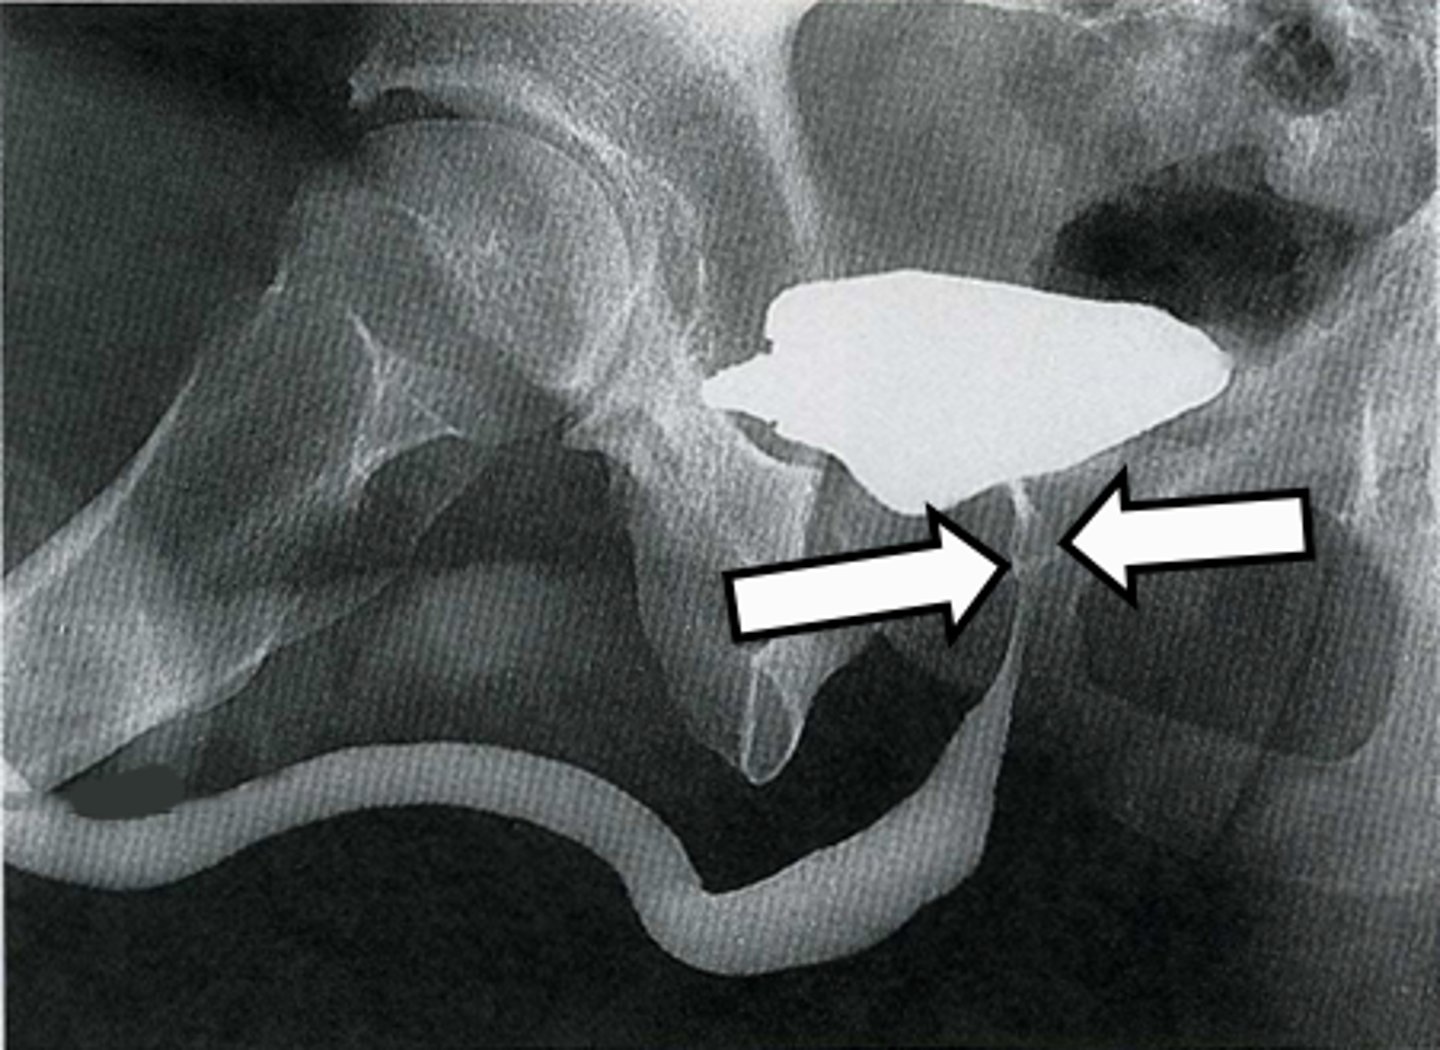

Voiding cystourethrogram

What is the image?

Bladder

What is indicated in the image?

Membranous urethra

Prostatic urethra

Spongy urethra